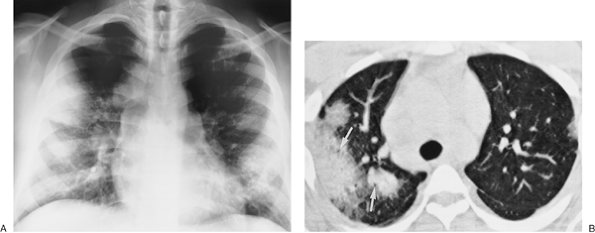

FIGURE 12-1. Usual interstitial pneumonitis. A: Posteroanterior (PA) chest radiograph of a 72-year-old woman with scleroderma shows low lung volumes and bilateral reticular interstitial lung disease. B: CT shows that the reticular opacities have a subpleural, peripheral distribution (arrows).

FIGURE 12-2. Eosinophilic pneumonia. A: PA chest radiograph of a 21-year-old woman shows bilateral airspace opacities that extend to the lung periphery. B: CT better shows the peripheral distribution of disease. Note prominent air bronchograms.

FIGURE 12-3. Alveolar sarcoidosis. A: PA chest radiograph of a 28-year-old asymptomatic man shows nonsegmental peripheral airspace disease and bilateral hilar and mediastinal lymphadenopathy. B: CT shows bilateral peripheral airspace disease. Note air bronchograms (arrows), a common feature of alveolar sarcoidosis.